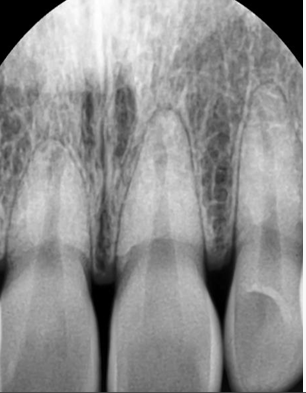

앞니 1개의 치아 뿌리가 다른 것보다 짧습니다. 이런 경우 교정을 하면서 치아에 힘을 주면 치아 뿌리가 더 짧아지는 치근흡수가

일어날 가능성이 있습니다. 그러나 꼭 교정을 하시고 싶으면 교정하는 것도 큰 무리가 아닐 수도 있습니다. 양악수술은 큰 수술이며

현재 상악 전치와 하악 전치의 뿌리의 길이가 정상적인 것보다 짧기 때문에 무리하게 후방견인을 하다가 치아 뿌리가 더 짧아지게 되면 나중에 잇몸뼈의 높이가 낮아지게 되었을 경우에 조기에 상실할수 있는 가능성이 있습니다.